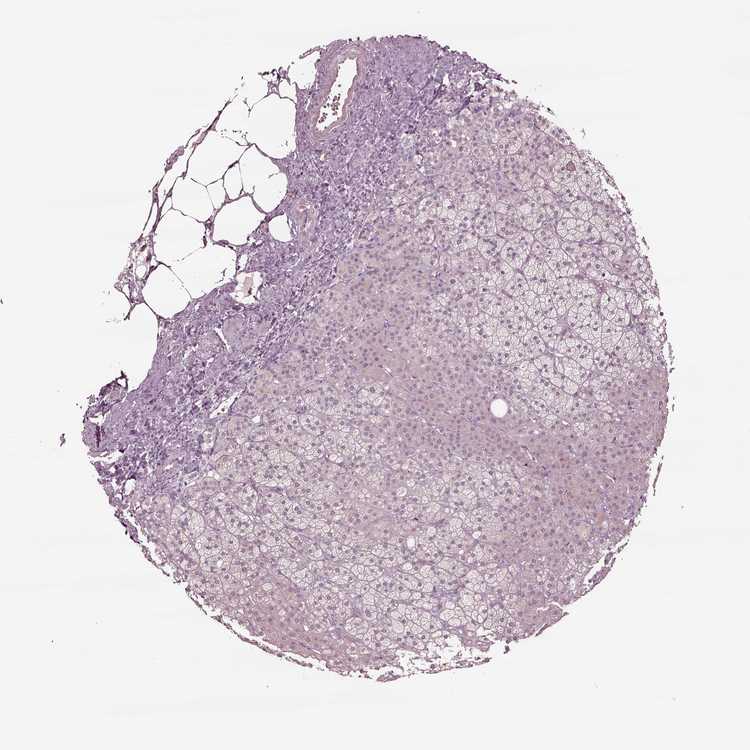

TISSUE PRIMARY DATA ADRENAL GLAND Show tissue menu

ADRENAL GLAND - Antibody stainingi

Antibody staining in the annotated cell types in the current human tissue is reported as not detected, low, medium, or high, based on conventional immunohistochemistry profiling in selected tissues. This score is based on the combination of the staining intensity and fraction of stained cells.

Each image is clickable and will lead to virtual microscopy that enables deeper exploration of all samples and also displays staining intensity scores, fraction scores and subcellular localization as well as patient and tissue information for each sample.

Antibody HPA042369

Glandular cells Not detected